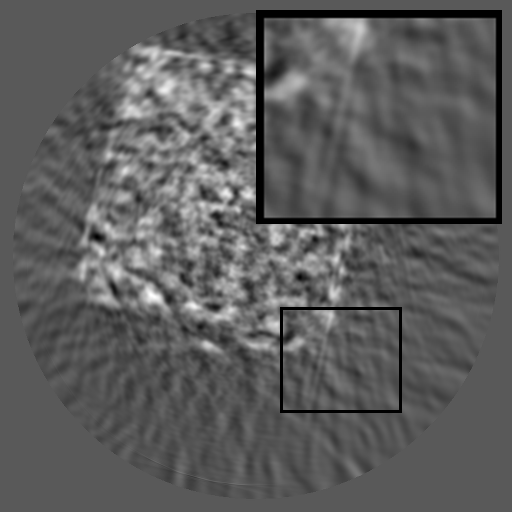

Refer to caption

(a) Mask

(b) SinoTx

(c) DiffIR

(d) HiDiffusion

(e) RePaint

(f) HRSino

(g) Ground Truth

Figure 3: Qualitative completion results on TomoBank (lines 1 to 2) and LoDoPaB (lines 3 to 4) with random mask (ratio = 0.8) at 1024×\times1024 resolution. Odd columns and even columns show the sinograms and reconstructed images, respectively.

4.2.3 Completion Quality

Tab 2 summarizes accuracy results. At 2048×\times2048 resolution, HRSino achieves the best performance among all baselines while remaining memory-efficient, demonstrating its ability to extend high-quality completion to resolutions where other diffusion models fail. At 1024×\times1024, HRSino delivers accuracy comparable to its computation-intensive counterpart RePaint, showing that our optimizations do not compromise fidelity at moderate scales. Compared to DiffIR, MCG, TD-Paint, and HiDiffusion, HRSino consistently achieves higher SSIM and PSNR across mask ratios, with improvements up to +0.03 SSIM and +1.8 dB PSNR. Fig 3 visualizes sinogram completion and reconstructed images, where HRSino produces nearly indistinguishable results from RePaint. These findings confirm that HRSino fundamentally extends diffusion-based completion to 2048×\times2048 resolution in a more memory- and runtime-efficient manner.